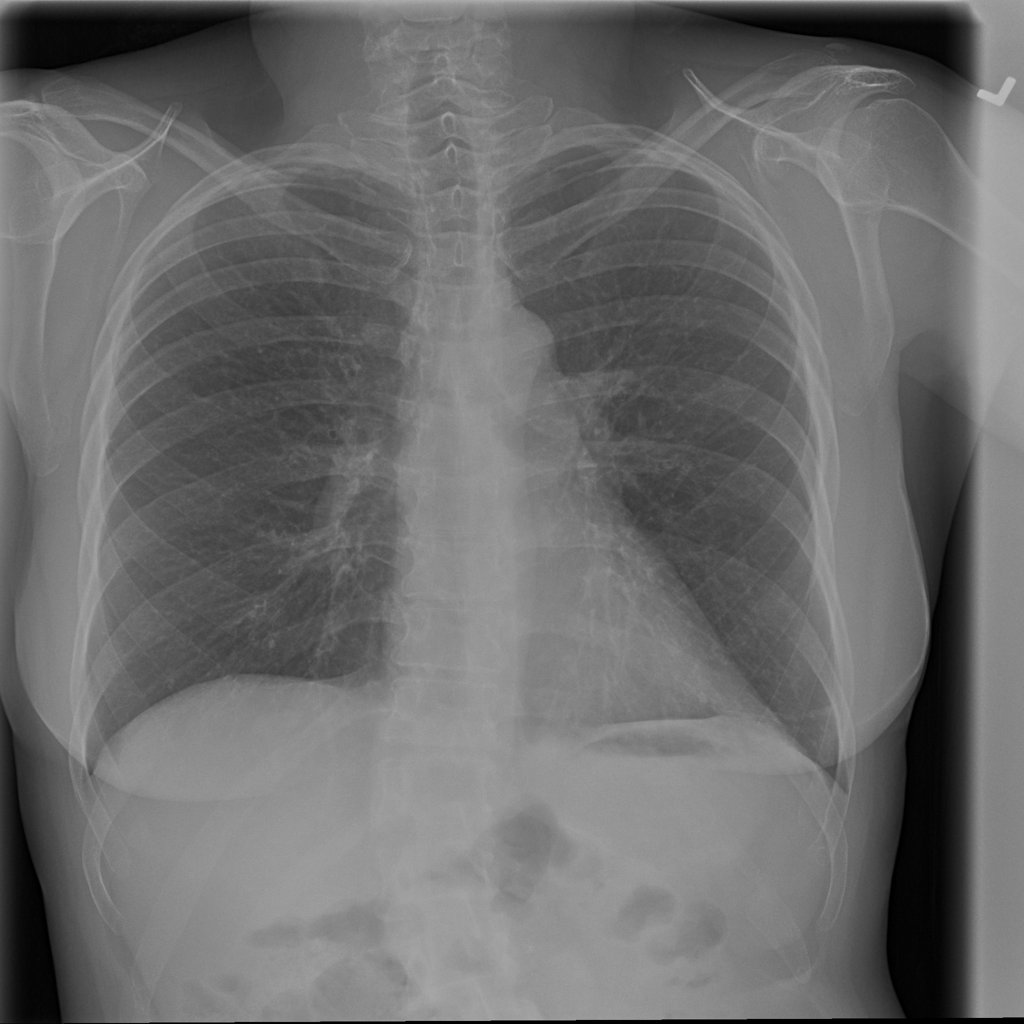

PAT-50E5 · IMG-002Effusion

PAT-50E5 · IMG-002

PA